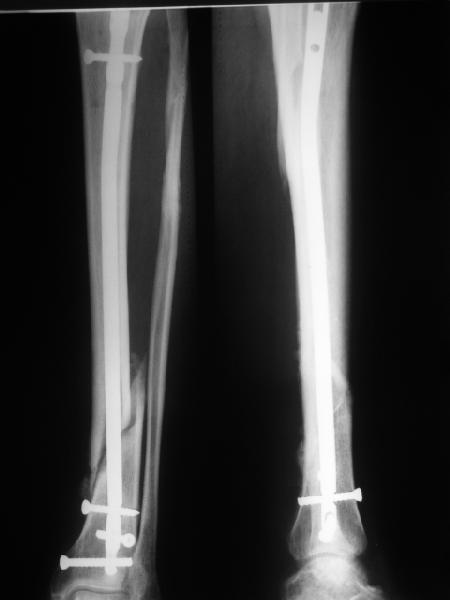

Антон, дорогой, важнее вальгуса тут близость верхнего отверстия к перелому и отсутствие уверенности в быстром сращении из-за большого

диастаза.

В Кемпбелле можно прочитать, что Fractures in the distal third of the tibia had the highest frequency of nail breakage.

Вообще, этот вопрос обсуждался давно, и еще в статье R. Bucholz (1987) про переломы гвоздей указывалось, что расстояние от ближайшего отверстия до перелома должно быть не менее 5 см, иначе есть угроза усталостного перелома. По литературе переломы гвоздей в нижней трети

tibia достигают 4,3%.